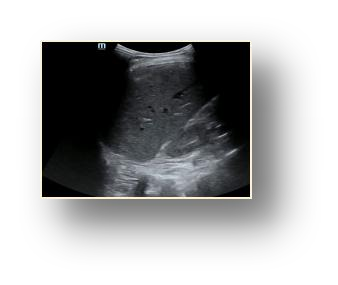

Most deep neural networks (DNNs) based ultrasound (US) medical image analysis models use pretrained backbones (e.g., ImageNet) for better model generalization. However, the domain gap between natural and medical images causes an inevitable performance bottleneck. To alleviate this problem, an US dataset named US-4 is constructed for direct pretraining on the same domain. It contains over 23,000 images from four US video sub-datasets. To learn robust features from US-4, we propose an US semi-supervised contrastive learning method, named USCL, for pretraining. In order to avoid high similarities between negative pairs as well as mine abundant visual features from limited US videos, USCL adopts a sample pair generation method to enrich the feature involved in a single step of contrastive optimization. Extensive experiments on several downstream tasks show the superiority of USCL pretraining against ImageNet pretraining and other state-of-the-art (SOTA) pretraining approaches. In particular, USCL pretrained backbone achieves fine-tuning accuracy of over 94% on POCUS dataset, which is 10% higher than 84% of the ImageNet pretrained model. The source codes of this work are available at https://github.com/983632847/USCL.

翻译:大部分深心神经网络(DNNS)基于超声波(美国)的超声波医学图像分析模型使用预先训练的脊椎(如图像网络)来进行更好的模型化分析。然而,自然图像和医疗图像之间的领域差距造成了不可避免的性能瓶颈。为了缓解这一问题,为在同一领域直接训练建造了一个名为US-4的美国数据集。该数据集包含来自四个美国视频子数据集的23 000多张图像。为了从美国-4中学习强健的特征,我们提议了美国半监督的对比学习方法,名为USCL(USCL),用于预培训。为了避免负面对子与有限的美国视频中丰富的地雷视觉特征之间的高度相似性,USCL采用了一种样品配对生成方法来丰富单步对比性优化所涉及的特征。关于一些下游任务的广泛实验显示了USCL对图像网络预培训和其他状态艺术预培训方法的优势。特别是,USCLU预先训练的骨架在POCS数据集上实现了94 %的微调精准性精确度,这在图像网络上比84%高10 %/MUSPASTASTASTRAIN premstrain practresmex pract press press rodustrismex sramduction sramduction sramduction sramduction surgles)。